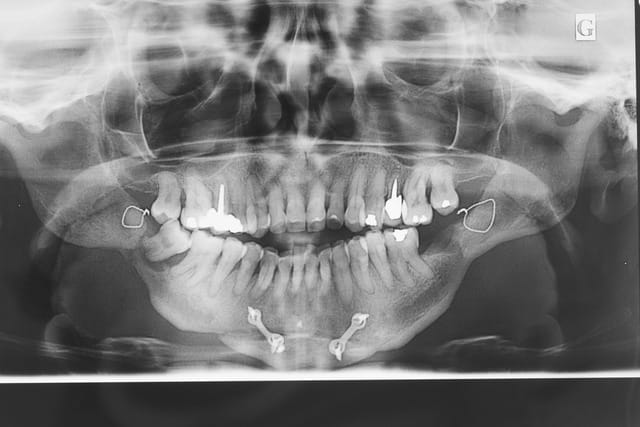

Patiente 58 ans à eu une chirurgie à visée esthétique et "fonctionnelle" adressée pour détartrage en urgence...je ne suis pas spécialiste mais je trouve que la greffe mentonnière est très bof

lésion apicale sur 42 risque de contamination sur la vis en regard..

Pourquoi trouves-tu la génioplastie bof?

Pour la persistance de l'image radiologique du trait d'ostéotomie? De quand date la chir?

Nous sommes d'accord pour la chirurgie mais secteur 4 il y a 2mm être là plastie et la mdble, ça ne me fais pas rêver

La lésion sur 42 était sans doute déjà là le jour de la chir... c'est plus ça qui craint effectivement.

42 nécrosée?

Parodontite stabilisée? (s'il y a plein de tartre ça craint aussi car c'est qu'elle n'a rien compris).

Nous sommes d'accord pour la genioplastie je me suis mal exprimé ce qui m'inquiète c'est la proximité de la greffe, pardon genioplastie et de l'infection de 42, d'une part et la mauvaise liaison de la genioplastie secteur 4, mais je suis peut-être pessimiste.

Plusieurs points: les vis de 15mm x 2mm qui transfixent c'est pas top, une seule plaque, qui plus est non réglable de chaque côté, c'est encore moins top. C'est une plaque de fracture.

En mandibulaire gauche c'est quoi ce fil d'osteosynthese? Un troisième fragment? En laissant l'apex de la 48 pile sur le trait d'osteotomie, je dis chapeau.

Pour la lésion de 42, ca peut être lié à la genio. Forage hasardeux? Mais je vote plus pour une lésion endo/paro

il y a de l'os autour de 11 et 21 ?

On dirait une chirurgie des années 90 :-(

Je ne suis pas fan des extractions multiple mais là, à part les secteurs molaires, je ne suis pas sur de pouvoir sauver quelques chose(surtout mandibulaire)